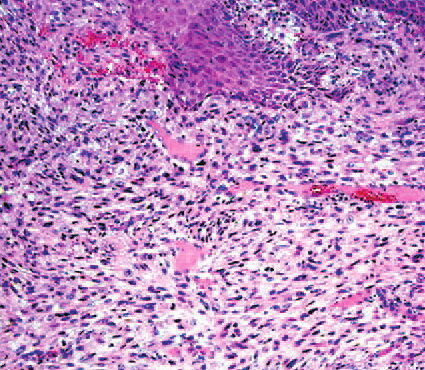

Read MoreForeign body reaction = ارتكاس للجسم الاجنبي Foreign Body Reactions Foreign substances, when injected or implanted accidentally into the skin, can produce a nonallergic foreign-body reaction or, in persons specifically sensitized to them, an allergic response (. In addition, certain substances formed within the body may produce a nonallergic foreign-body reaction when deposited in the […]